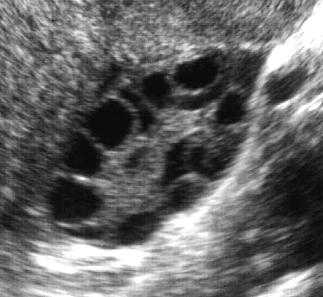

Синдром, связанный с гормональным дисбалансом в гипофизе и приводящий к развитию ожирения либо изменению телосложения на «спортивный тип» с широкими плечами и узким тазом, недоразвитию молочных желёз, чрезмерного оволосения, появлению акне, снижению тембра голоса. Причиной таких клинических проявлений служит повышение уровня ЛГ (лютеинизирующего гормона) в гипофизе, который стимулирует синтез андрогенов в яичниках и возникает гиперандрогения (чрезмерное количество мужских половых гормонов в организме женщины). Также одним из проявлений будут нерегулярные мажущие кровотечения вместо полноценных ментсруаций из-за того, что при недостатке эстрогенов эндометрий не может нормально расти и отторгаться в период менструаций.